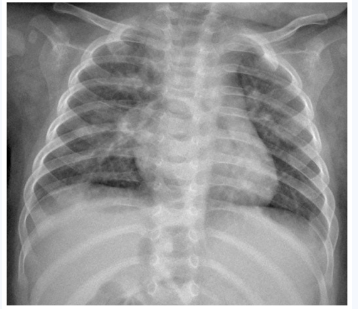

图1 双肺纹理增粗、模糊,双肺并见散在小斑片状淡薄阴影,边界不清,以双肺内中带分布明显。双侧肺门不大,结构模糊。

图1

图1 病毒性肺炎